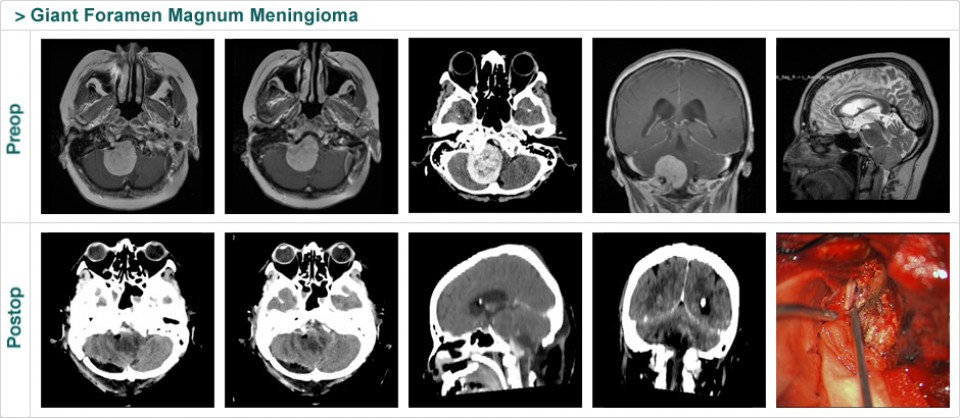

Dr. Attia is an attending neurosurgeon and the director of skull base surgery service in the department of neurosurgery at Sheba Medical Center in Tel HaShomer. His specialty focuses on skull base and cerebrovascular neurosurgery.